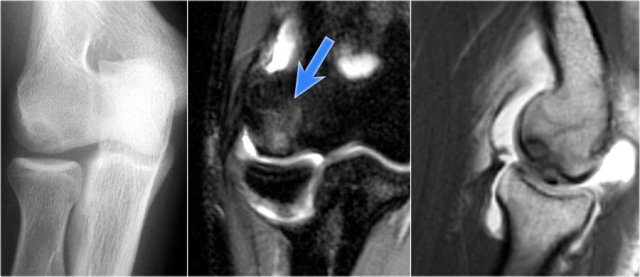

Here we see two consecutive coronal images of the UCL.

It is normal to see some high signal in the proximal part (arrow).

Notice how it firmly attaches to the sublime tubercle and compare this to the next images.

UCL tear

Remember that the UCL should attach very tightly on the sublime tubercle.

In this case it doesn't, so even on these two images you can tell that there is a complete tear.

Notice that there is some marrow edema in the sublime tubercle.